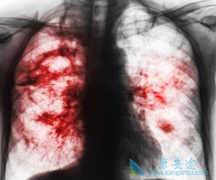

非小细胞肺癌(NSCLC)是一种最常见的肺癌,占全部肺癌病例的85%以上。SCC是一种可在呼吸道壁层细胞中发生的肺癌,约占NSCLC病例的30%。 由于治疗选择有限以及SCC不良预后,晚期SCC患者能够存活5年或5年以上的比例不到5%。据了解,在宣布的LUX-Lung 8 试 ...